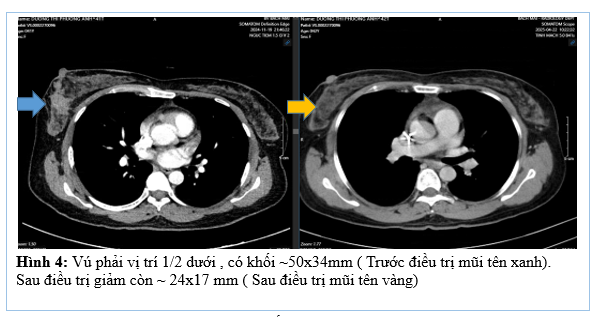

– CT ngực trước điều trị

– CT ngực trước và sau điều trị tân bổ trợ

Như vậy sau 6 chu kì điều trị tân bổ trợ phác đồ TCHP cho thấy bệnh đáp ứng một phần, u và hạch giảm đáng kể kích thước. Bệnh nhân được chỉ định cắt toàn bộ tuyến vú phải và vét hạch nách (5/2025)